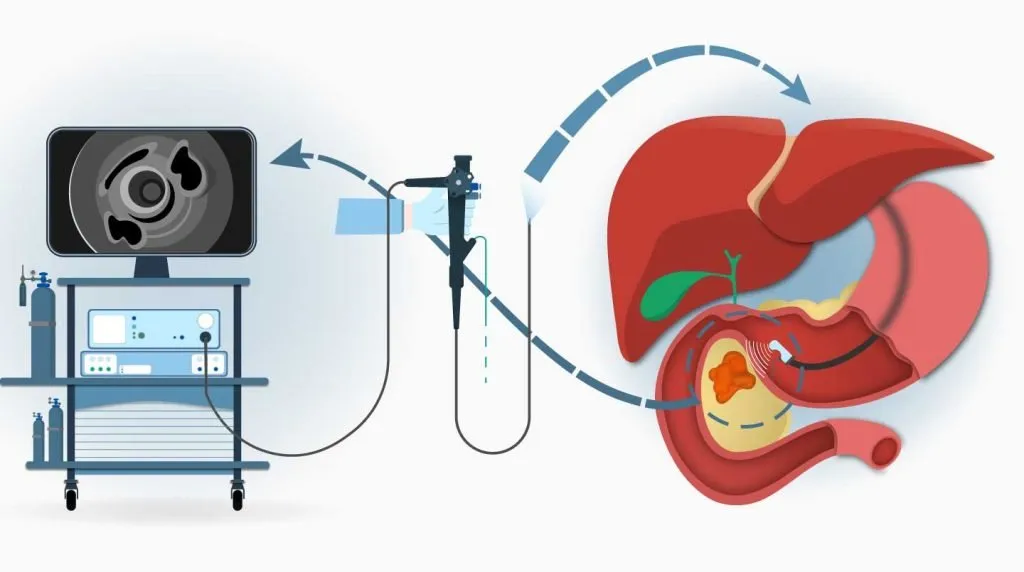

A specialized procedure used to diagnose and treat disorders of the bile ducts and pancreas. Common indications include: